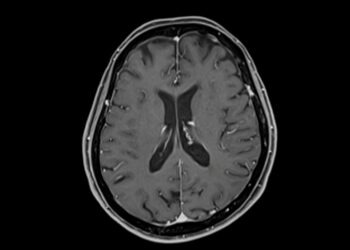

Skaityti daugiauDetails3 laipsnio astrocitoma, dar vadinama anaplastine astrocitoma, – tai piktybinis, sparčiai augantis galvos smegenų auglys. Jis vystosi iš astrocitų –...